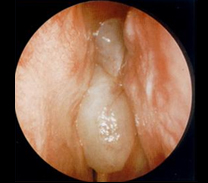

| Orrpolip orrtükri képe. |

Tipikus az orrtükri kép. Az orrpolipok egyszeresen vagy többszörösen helyezkedik el. Diagnózisát a fül-orr-gégész viszonylag könnyen megállapítja az orrtükri kép alapján.

A képen jól látható az endoszkópos vizsgálat, amelynek során pontos képet kapunk az orrüreg és a melléküregek bemeneti nyílásainak állapotáról.